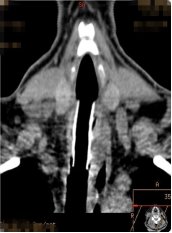

术前

经过术前的充分准备,患者在全麻下,用可弯曲支气管镜引导插入法插入硬镜,通过高频电刀放射状切开狭窄环,再予气道球囊扩张器扩张气道置入硅酮支架,并置入喉罩复苏,最后成功为患者实施硬质支气管镜技术。术后,患者气道通畅,无呼吸困难、气促等症状出现,对比术前生活质量得到明显改善。

高频电刀切开狭窄环